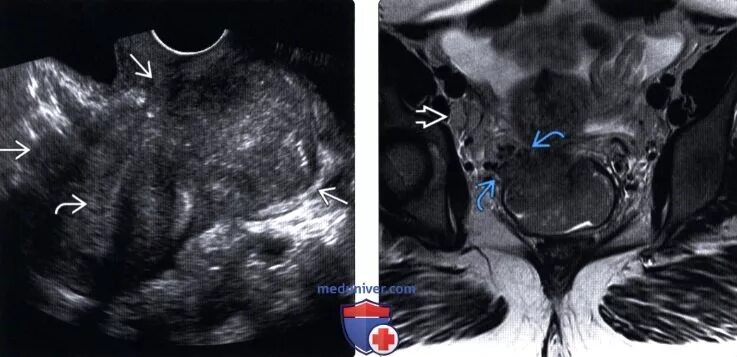

Гематометра симптомы